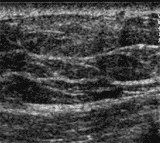

Bild vergrößern

Ultraschall der Brust